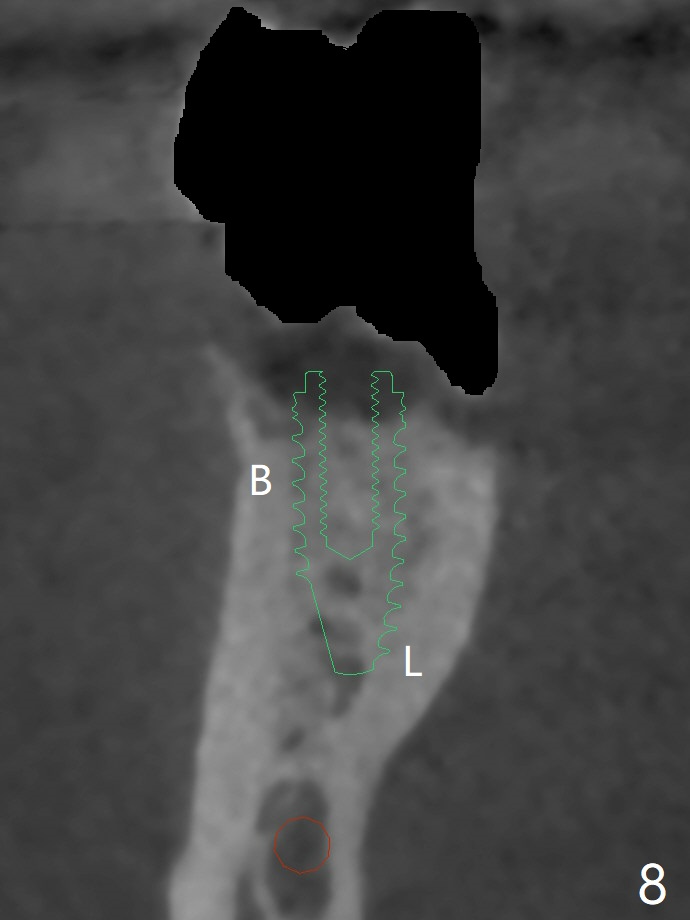

A 65-year-old man has nocturnal pain associated with #30 lingual furca caries and gingival recession (Fig.1,2). PRF (x2) and sticky bone will be used to repair the lingual soft and hard tissue defects. CT shows the submandibular fossa (Fig.3 <), dictating a short implant 10 mm, Fig.4). To place the implant in the septum (Fig.3 S), the coronal portion of the tooth is removed (Fig.5 black area) so that the roots are able to keep the osteotomy without deviation (Fig.6 red arrow). It is possible to place the implant in a trajectory mesiodistally (Fig.7 in fact after root extraction (arrows)). To prevent buccolingual deviation, a small implant (4 mm in diameter) is designed so that it will NOT touch the buccal (B in Fig.8) or lingual (L) plates. The bone density of the cortex and medulla is 2000 and 1400 units, respectively. To reduce the chance of implant fracture because of the narrow diameter in function, an implant with Titanium V will be used.